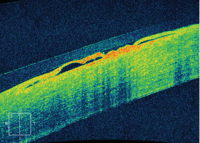

► Optical coherence tomography (OCT) is one example. Today’s widely used OCT instruments allow the capture of cross-sectional images of ocular tissue structure with resolution as high as 3 microns.

That’s a really close look when you consider that a micron is one-millionth of a meter. One inch contains about 25,000 microns, and the eye of a needle contains about 1,200 microns.

OCT has replaced more invasive diagnostic tests as the primary way of monitoring the progression of many retinal conditions and diseases and their response to treatment. OCT also provides high-resolution visualization of anterior segment structures such as the cornea and angle, and measures the thickness of the retinal nerve fiber layer to aid in the diagnosis and monitoring of glaucoma and other diseases of the optic nerve. Anterior segment